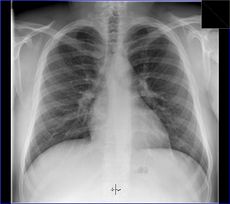

Poté, co Röntgen objevil využití pro pozorování kostních struktur, se rozvinulo jeho užívání v lékařském snímkování. Rentgenové záření může být využito pro zobrazení detailů kostí a zubů (skiagrafie), popřípadě za pomoci vhodných technik i ke zkoumání měkké tkáně (denzitografie, subtrakční skiagrafie, tomografie). Radiologie je specializovaný obor lékařství využívající rentgenového záření v diagnostice. Toto je pravděpodobně nejčastější využití rentgenového záření.